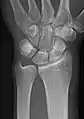

- Wrist - DP and Lateral

Left wrist by dorsoplantar projection

Lateral projection

- Scaphoid - DP with Ulna deviation, Lateral, Oblique and DP with 30° angulation